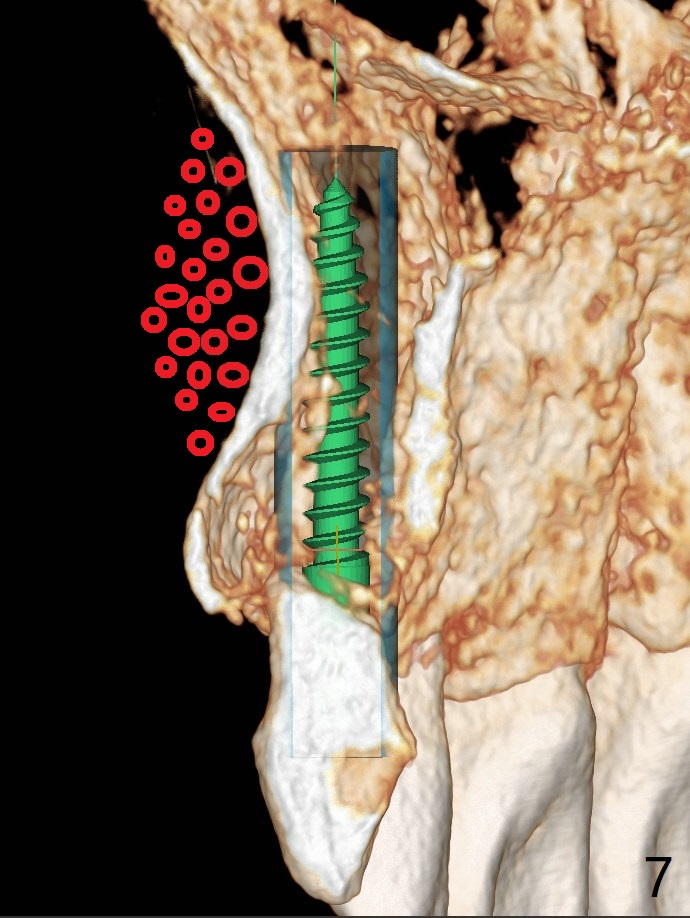

Since there is limited vertical and horizontal (buccopalatal) space at H, it appears that 1-piece implant may offer simple treatment to avoid angled abutment (Fig.1). Because of the thin concave buccal plate over the narrow implant (Fig.2,3,4 *), a remote incision will be made immediately post implantation (Fig.5 red line). After subperiosteal dissection, bone graft will be deposited to avoid implant thread exposure and restore the canine prominence (Fig.6,7). Prepare PRF for sticky bone. Take preop photo to show buccal apical concavity.